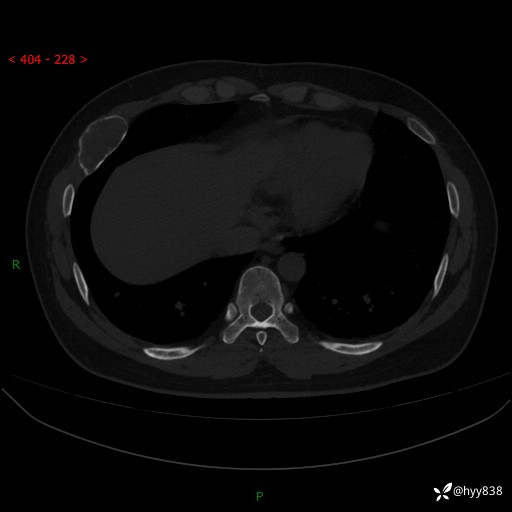

年轻小伙,右侧胸部疼痛4天余。病理科说肯定不是骨纤,那是啥---结果公布~

年龄:24岁

主诉:右侧胸部疼痛4天余。

现病史:患者约4天前突发右侧胸部疼痛,无瘙痒,无头痛、头晕,无心慌、胸闷、呼吸困难、咳嗽、咳痰、咯血,无腹痛、腹胀等不适,未作进一步诊治。于2024年5月外院行胸部CT平扫示右侧肋骨骨质改变。现为求进一步治疗,遂于我院就诊。门诊以“胸壁肿物”收入我科。 患者自起病以来,精神可,睡眠可,饮食可,大小便正常,体重无明显改变。

胸部CT平扫